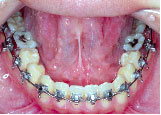

下の歯が上の歯より前に出て前歯は咬めていません。左上の第2小臼歯は骨の中に埋まっています。

また下あごは左にずれています。顎変形症、下顎前突と診断しました。

クォードヘリックスで上顎歯列を左右へ拡げた後、右上第1小臼歯を抜歯し、エッジワイズブラケットを付けて術前矯正を始めました。

骨の中に埋まっている左上の第2小臼歯は手術の時に抜いてもらいます。